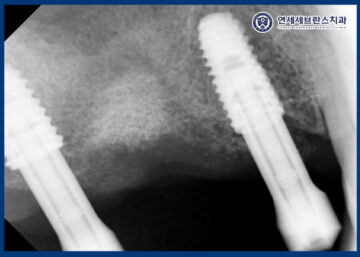

CT로 비교해 보았을 때,

상악동거상술을 통해

부족했던 상악동 하방 공간을 확보하여

임플란트 식립이 가능한 환경을

조성한 것을 확인할 수 있었습니다.